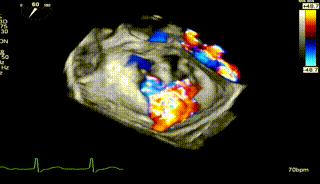

怎么上穿刺鞘攻克巨大左房伴转位穿刺难关!温医大附一院周浩教授团队创新应用“导丝定位+可调弯鞘”技术完成高难度TEER手术_https://www.jmylbn.com_新闻资讯_第8张

3D

怎么上穿刺鞘攻克巨大左房伴转位穿刺难关!温医大附一院周浩教授团队创新应用“导丝定位+可调弯鞘”技术完成高难度TEER手术_https://www.jmylbn.com_新闻资讯_第9张

3D带彩